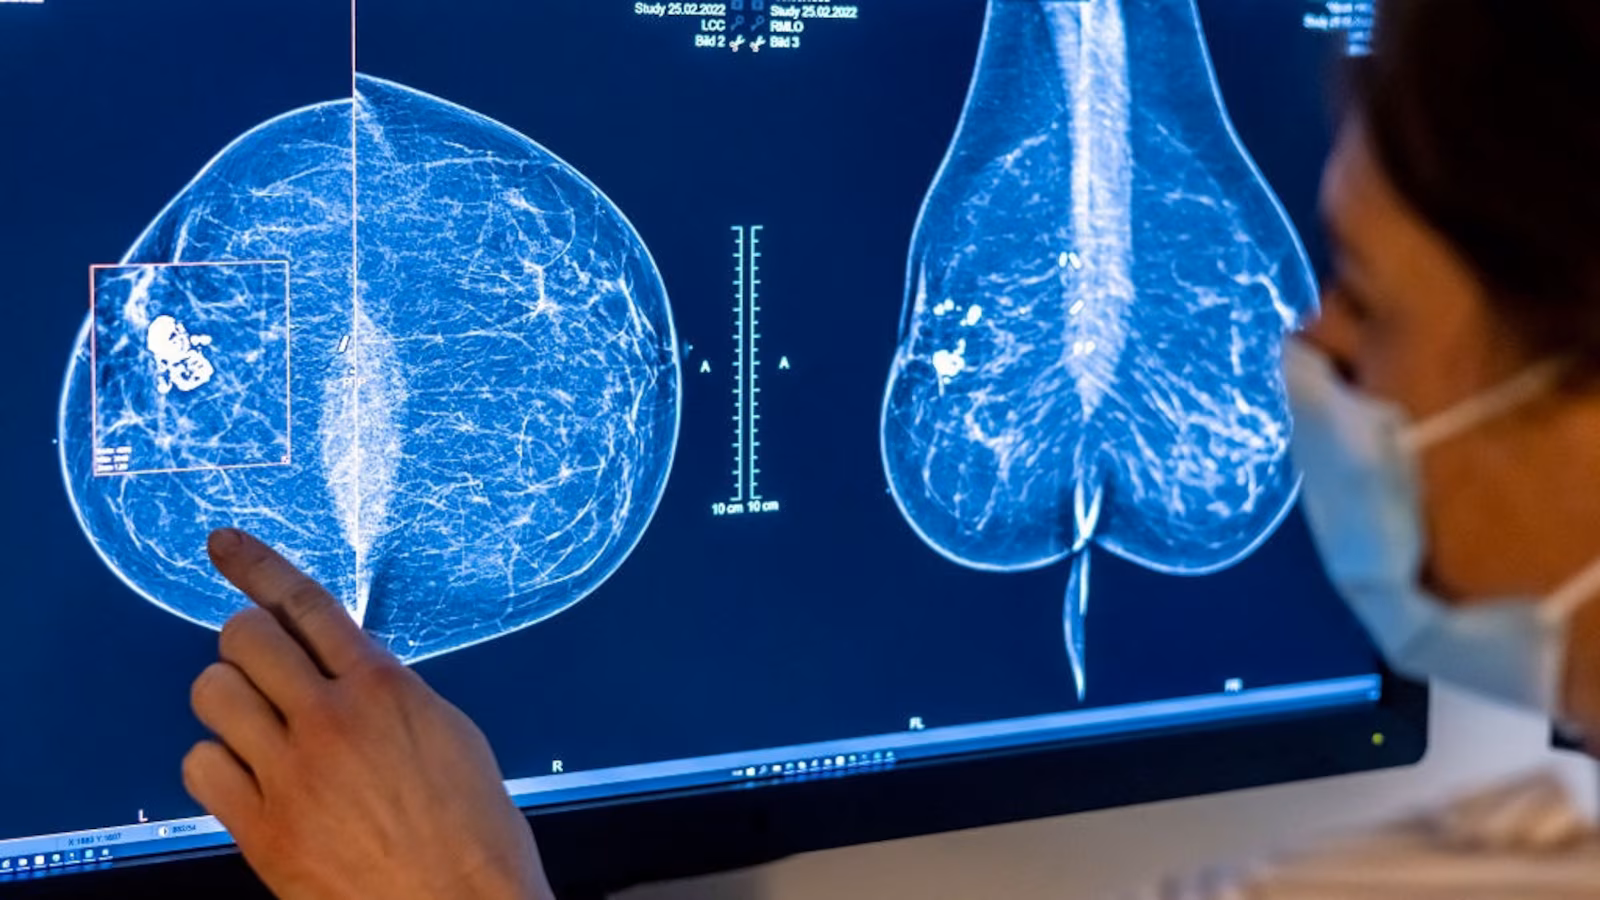

Medical personnel use a mammogram to examine a woman’s breast for breast cancer. Photo: Hannibal Hanschke/dpa

Picture Alliance/dpa/picture alliance via Getty I